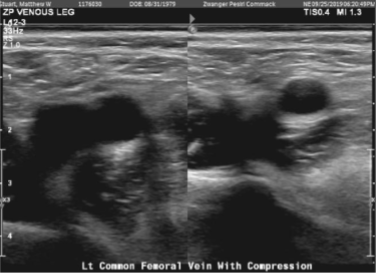

Doppler venous left lower extremity

There are findings consistent with deep vein thrombosis of the left leg. Specifically, there are findings consistent with deep vein thrombosis involving the visualized posterior tibial venous system. The appearance is consistent with acute deep vein thrombosis.